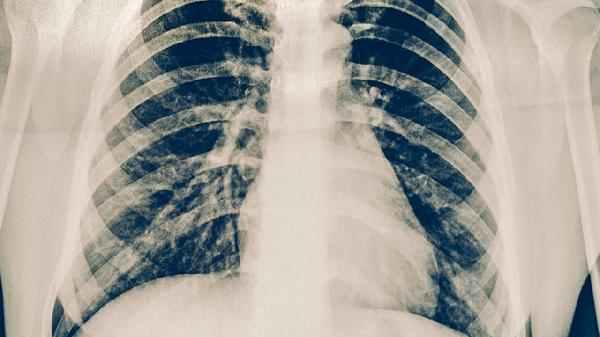

肺积水胸腔积液的严重程度取决于病因和积液量,轻度积液可能由肺炎等感染引起,大量积液可能提示心力衰竭、恶性肿瘤等严重疾病。

结核性胸膜炎或细菌性肺炎是常见病因,积液量通常较少,伴随发热、咳嗽等症状。通过抗感染治疗和胸腔穿刺引流可有效控制,多数预后良好。

心力衰竭导致肺静脉压力升高时,会出现双侧胸腔积液,可能伴有呼吸困难、下肢水肿。需利尿剂治疗原发病,积液量大时需穿刺抽液。

肺癌胸膜转移或恶性胸膜间皮瘤可引起血性胸腔积液,常伴随消瘦、胸痛。需通过胸水细胞学检查确诊,治疗包括胸腔灌注化疗和全身治疗。

肝硬化或肾病综合征患者因血浆胶体渗透压降低,出现双侧漏出性积液。需补充白蛋白并治疗原发病,积液多能自行吸收。

系统性红斑狼疮等疾病可能引发胸腔积液,通常伴有关节痛、皮疹。糖皮质激素治疗可缓解症状,需长期免疫调节治疗。

肺积水患者应限制钠盐摄入,每日食盐量控制在3克以内,适量补充优质蛋白如鱼肉、蛋清。保持半卧位休息有助于减轻呼吸困难,监测每日尿量和体重变化。急性期避免剧烈运动,恢复期可进行散步等低强度有氧运动。出现呼吸急促、血氧下降等表现时需立即就医,反复发作或病因不明者建议定期复查胸部影像学。